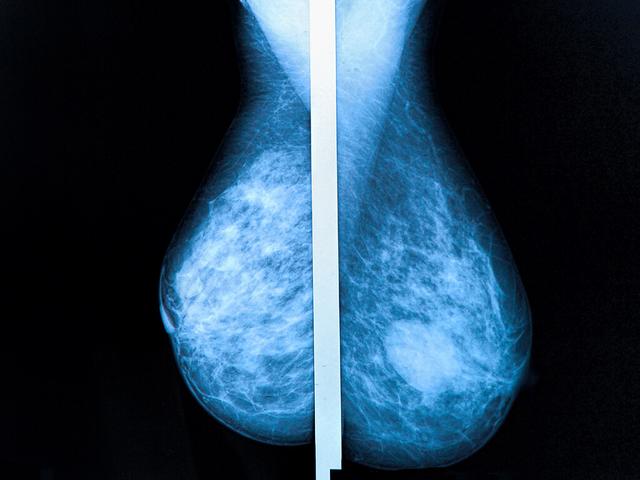

Der Ultraschall der Brust wird oft als Ergänzung zur Mammographie eingesetzt, insbesondere wenn Ärzte die Röntgenbilder nicht sicher beurteilen können. Während die Mammografie die beste Methode ist, um Veränderungen in der Brust festzustellen, kann der Ultraschall wertvolle Zusatzinformationen liefern.

Die Bedeutung von Ultraschalluntersuchungen nach einer Mammographie liegt darin, dass sie zusätzliche Informationen liefern können, wenn die Mammografie-Röntgenbilder nicht eindeutig sind. In bestimmten Fällen können Ärzte und Ärztinnen durch den Ultraschall besser beurteilen, ob es sich bei verdächtigen Befunden um flüssigkeitsgefüllte Zysten oder um Gewebeknoten handelt. Besonders bei Frauen mit bindegewebsreicher Brust, wie jungen Frauen vor den Wechseljahren, ist der Ultraschall aussagekräftiger als die Auswertung von Mammografie-Aufnahmen.

Ultraschalluntersuchungen werden auch als Sonographie oder Echographie bezeichnet und sind strahlungsfrei. Sie können in vielen Bereichen der Medizin eingesetzt werden, um verschiedene Organe und Gewebe zu untersuchen. Beim Brustultraschall werden Gewebe je nach Dichte in unterschiedlichen Helligkeitsstufen dargestellt. Flüssigkeitsgefüllte Strukturen wie Zysten erscheinen eher schwarz, während stark reflektierende Strukturen wie Kalk oder Knochen weiß angezeigt werden.

Es ist wichtig zu beachten, dass der Ultraschall alleine meist nicht ausreicht, um Brustkrebs sicher nachzuweisen. Die Mammografie bleibt die beste Methode zur Feststellung von Veränderungen in der Brust. Der Ultraschall kann jedoch wertvolle Zusatzinformationen liefern und bei unklaren Befunden helfen, eine Biopsie zu vermeiden.